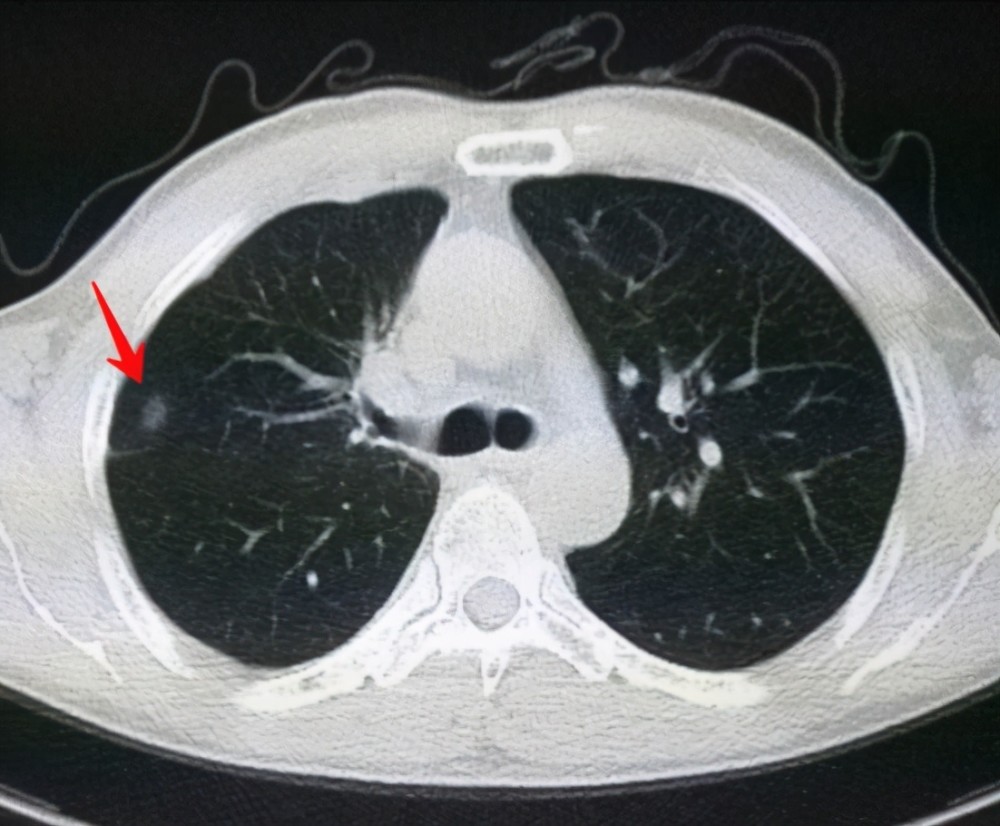

6、定期體檢:定期進(jìn)行肺部檢查,及時(shí)發(fā)現(xiàn)并治療肺結(jié)節(jié)。

對于已經(jīng)發(fā)現(xiàn)肺結(jié)節(jié)的患者,應(yīng)及時(shí)就醫(yī),進(jìn)行進(jìn)一步的檢查和治療,醫(yī)生會(huì)根據(jù)患者的具體情況制定個(gè)性化的治療方案,包括藥物治療、手術(shù)治療等,早期發(fā)現(xiàn)、早期治療是提高肺結(jié)節(jié)治愈率的關(guān)鍵。